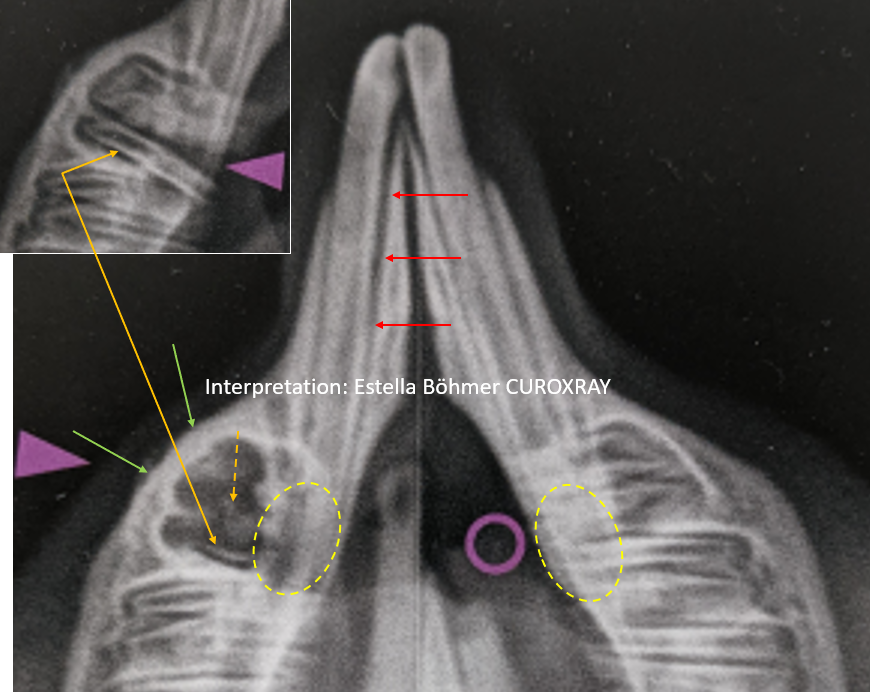

Gezeigt wird eine mehr oder weniger symmetrisch gelagerte Unterkiefer isoliert Aufnahme nach Böhmer (siehe Beitrag vom 9-4-2022), die einen längsgespaltenen ersten mandibulären Backenzahn (P4) zeigt (dicker lila Pfeil des Autors). Der Autor bezeichnet dies irrtümlicherweise (?) oder bewusst (?) als „Zahnfraktur“. Eine Fraktur ist in aller Regel die Folge eines Traumas oder eines Ermüdungsbruches bei normaler Belastung. Dies ist bei diesen typischen Längsspaltungen der Backenzähne von Heimtieren jedoch nicht der Fall. Es handelt sich gewissermaßen um eine Separation der jeweiligen Dentinsäulen als Folge der apikalen Entzündung.

Dann wird noch erwähnt, dass der „OK re Inzisivus (101) abgebrochen ist (lila Kreis)“. Außer Acht lassend, dass der Pfeil neben dem kürzeren maxillären Schneidezahn liegt`und nicht im Bereich der fehlenden klinisch sichtbaren Krone, fällt auf dem Röntgenbild auf, dass die Alveole deutlich erweitert ist (roter Pfeil). Man könnte nun annehmen, dies sei durch die leicht asymmetrische Lagerung bedingt. Jedoch ist die periodontale Erweiterung auch auf der besser gelagerten postoperativen Aufnahme erkennbar (gestrichelter roter Pfeil). Somit muss dies ernst genommen und diagnostisch weiter verfolgt werden! Im übrigen stellt sich ja auch die Frage, ob der Zahn wirklich abgebrochen ist oder ob der Inzisivus infolge einer apikalen Infektion sein Wachstum einfach nur eingestellt hat.

Keine Erwähnung findet weder im Text noch in den Bildunterschriften die Tatsache, dass der linke mandibuläre Schneidezahn eine unphysiologische Krümmung ausweist (hellgrüne Linie). Man könnte wieder argumentieren, dass dies nur lagerungsbedingt sei? Es ist jedoch auch auf der symmetrisch gelagerten postoperativen Aufnahme erkennbar (hellgrüner Doppelpfeil). Somit ist es ein eindeutiger radiologischer Befund, der sicherlich auch im Rahmen einer sorgfältigen klinischen Diagnostik der Zähne auffällt. Es muss geklärt werden, was die primäre Ursache für die abnorme Krümmung dieses Zahnes ist (?), in dessen Nähe sich auch ein hochgradig pathologisch veränderter Backenzahn befindet. Hängen beide Veränderungen zusammen? Ein Blick auf den Apex des linken mandibulären Schneidezahnes lässt erkennen, dass sich dieser Bereich im Vergleich zur anderen Seite röntgentransparenter darstellt (gelber gestrichelter Kreis). Der apikale Teil des Schneidezahnes scheint zum größten Teil zu fehlen = apikale Lyse = apikale Infektion. Dies muss mit Hilfe weiterer gezielter gezielter Röntgenaufnahmen (Schrägaufnahme UK isoliert nach Böhmer) nachgewiesen oder ausgeschlossen werden (Details zur Lagerung siehe in meinem Zahnbuch). Alles zusammen berücksichtigend denke ich, dass es recht eindeutig eine Schneidezahninfektion ist, da ein erweitertes Periodont hinzu kommt (rote Pfeile) und sich der apikale Bereich auch postoperativ röntgentransparenter darstellt (gelbe gestrichelte Kreise).

Die alleinige Backenzahnextraktion wird nicht ausreichen die lokale Knocheninfektion zur Abheilung zu bringen, die mit einer deutlichen reaktiven Verdickung des Mandibulaknochens einhergeht (hellgrüne Pfeile). Zumal in der Alveole ein verbliebener Zahnrest (vermutlich Teil der kaudalen Schmelzkante erkennbar ist (orangener Pfeil). Beim restlichen intraalveolären Gewebe (orangener gestrichelter Pfeil) könnte es sich um kleine Dentinanteile oder kleine Knochenfragmente handeln. Insgesamt muss man somit konstatieren, dass die alleinige und in dieser Form durchgeführte Extraktion des Prämolaren keinen Sinn ergibt. Aller Erfahrung und Wahrscheinlichkeit nach wird der Infektionsbereich unter dieser „Anbehandlung“ nicht komplikationslos abheilen. Nachversorgungen werden erforderlich sein und das ist weder für den Patienten noch den Besitzer zumutbar.